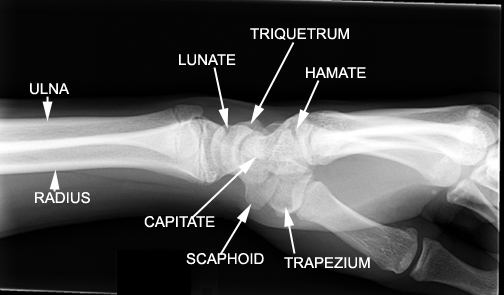

Identify the carpal bones. Click the image for labeling.